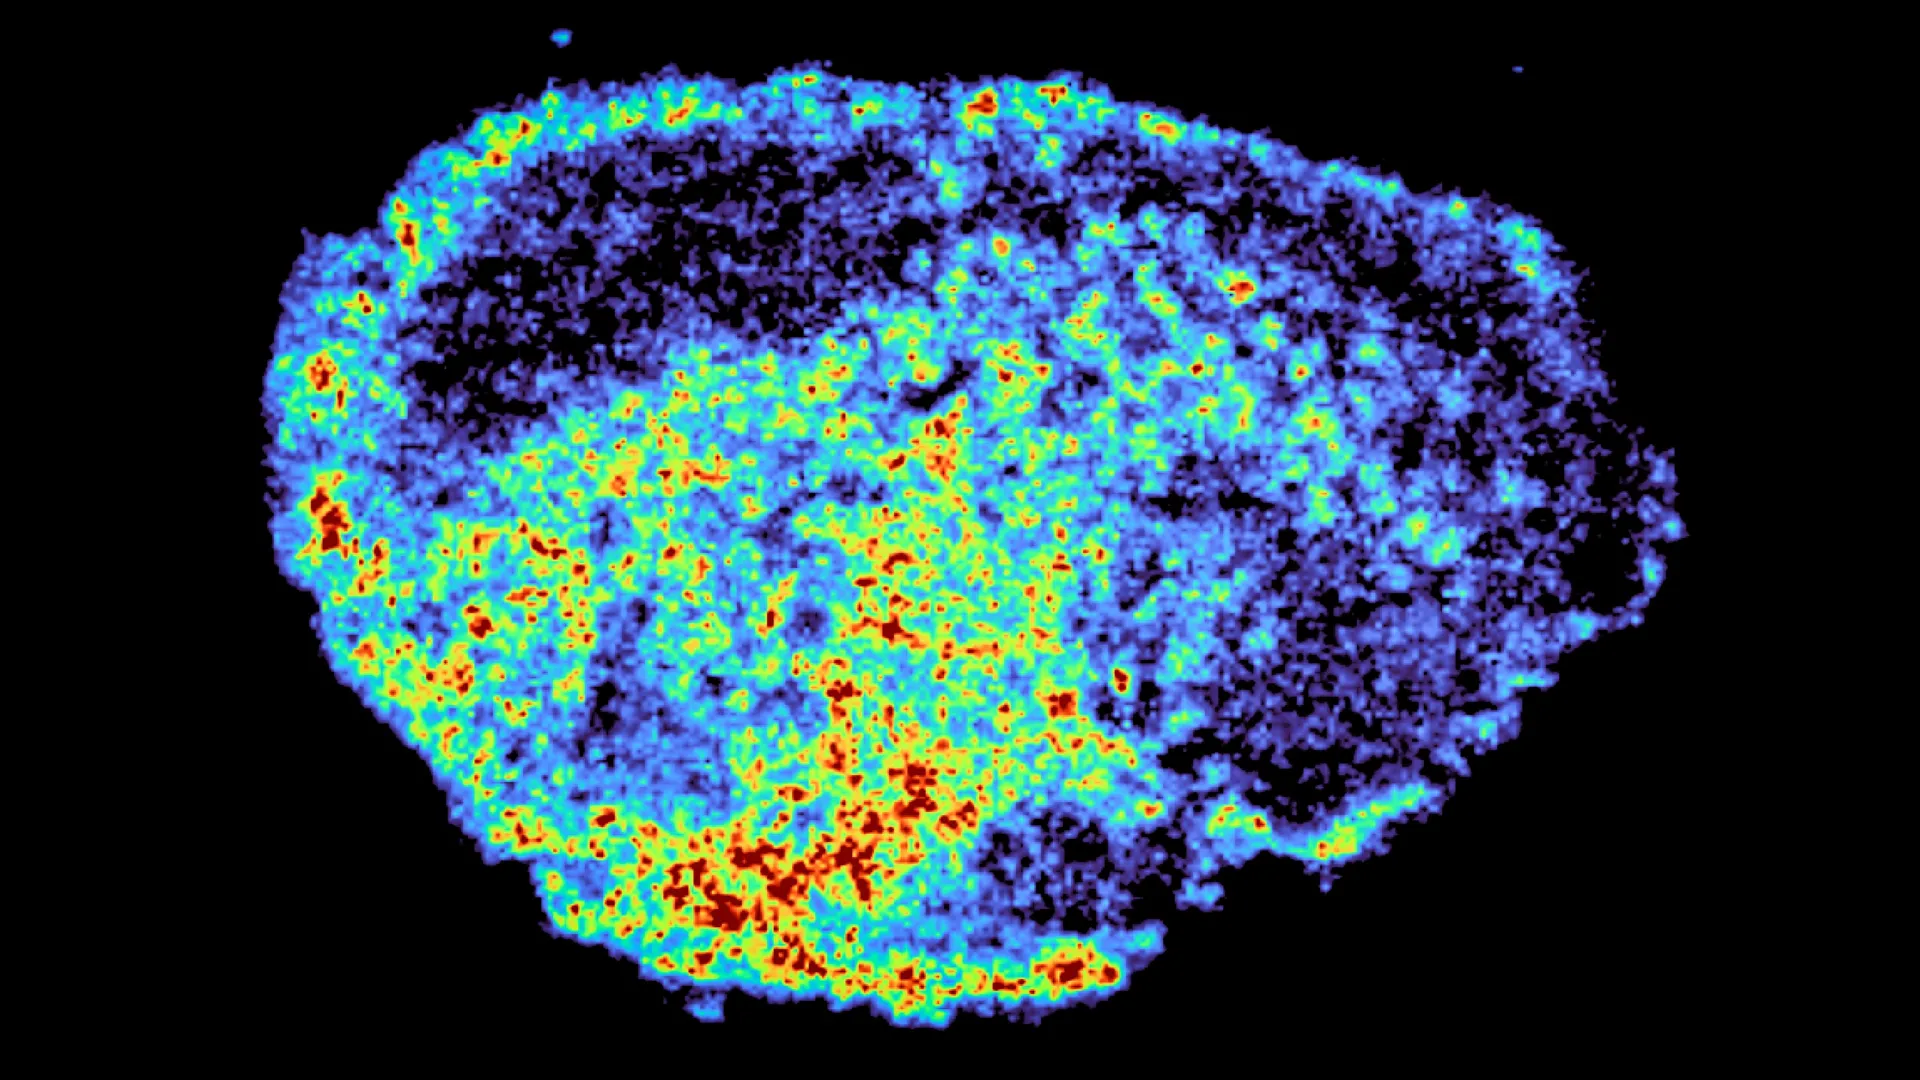

Foto: MRC Laboratory of Medical Sciences

Studie, kterou vedla Dr. Louise Fets v MRC Laboratory of Medical Sciences a která byla publikována v časopise Nature Communications, se zaměřila na PARP inhibitory, což je třída cílených léků na rakovinu. Výzkumníci sledovali, jak se tyto léky pohybují skrze vzorky ovariálních nádorů pomocí pokročilých zobrazovacích nástrojů. Zjistili, že léky se mohou hromadit uvnitř lysozomů, malých struktur uvnitř buněk, které fungují jako „recyklační centra“. Jakmile se léky dostanou dovnitř, mohou se zachytit a později uvolnit, což ovlivňuje účinnost léčby.

Výzkumníci použili tenké plátky ovariálních nádorů odebraných od pacientů a udržovaných naživu v laboratoři. Tyto vzorky, známé jako „explantáty“, byly ošetřeny PARP inhibitory, aby vědci mohli přímo pozorovat, jak se léky pohybují skrze skutečnou lidskou nádorovou tkáň. Pomocí hmotnostní spektrometrie vytvořili detailní mapy ukazující přesně, kde se léky hromadí. Spojili to s prostorovou transkriptomikou, která jim umožnila zkoumat genovou aktivitu v oblastech s vysokými a nízkými úrovněmi léků ve stejném vzorku.

Výzkumníci objevili, že lysozomy hrají klíčovou roli v této nerovnoměrné distribuci. Některé PARP inhibitory jsou vtahovány do těchto kompartmentů a ukládány tam místo toho, aby se rovnoměrně rozšířily po celé buňce. To vytváří vnitřní kapsy, kde se léky hromadí. Tyto lysozomy fungují jako rezervoáry s pomalým uvolňováním – drží lék a postupně ho uvolňují – což zvyšuje expozici v určitých buňkách, zatímco jiné zůstávají s mnohem nižšími úrovněmi.

Ne všechny PARP inhibitory se chovají stejně. Studie zjistila, že léky jako rucaparib a niraparib jsou tímto procesem ovlivněny, zatímco jiné, jako olaparib, nikoliv. „Byli jsme překvapeni velkou variabilitou v akumulaci léků na úrovni jednotlivých buněk. Tato variabilita byla způsobena hromaděním léku v lysozomech, které fungují jako rezervoáry, zvyšující expozici rakovinných buněk lékům tím, že lék ukládají a uvolňují, když je to potřeba,“ říká Dr. Carmen Ramirez Moncayo, první autorka a postdoktorandka v LMS.